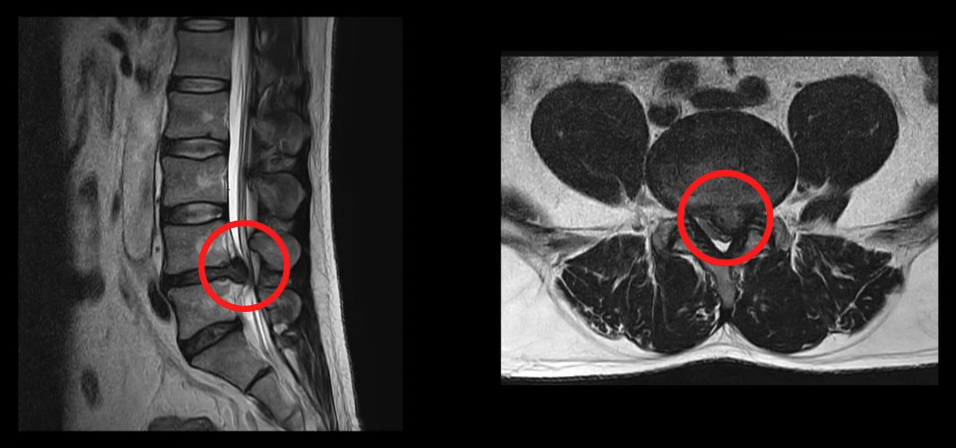

<4-5번 디스크 파열>

이 환자분은 요추 4-5번에 매우 심한 디스크 파열이 있으며, 특히 밀려나온 디스크 수핵이 척추관의 공간을 약 2/3 정도 차지하고 있는 상황이었습니다.

MRI 상으로 봤을 때도 통증은 물론 마비와 대소변 장애까지 의심될 수 있는 심각한 상황으로, 역시나 환자분도 발목과 발가락의 마비와 힘 빠짐 및 대소변 장애 증상을 호소하였습니다. 당연히 걷는 것은 물론 반듯하게 누울 수도 없는 상태였고, 타 병원에서 바로 수술을 받아야 한다는 말을 들었으나 비수술적인 치료를 받기 위해 모커리에 내원하셨습니다. 이런 상태의 환자분이 한방재활치료로 어떻게, 얼마나 좋아질 수 있는지 환자분의 얘기를 직접 들어보시죠.